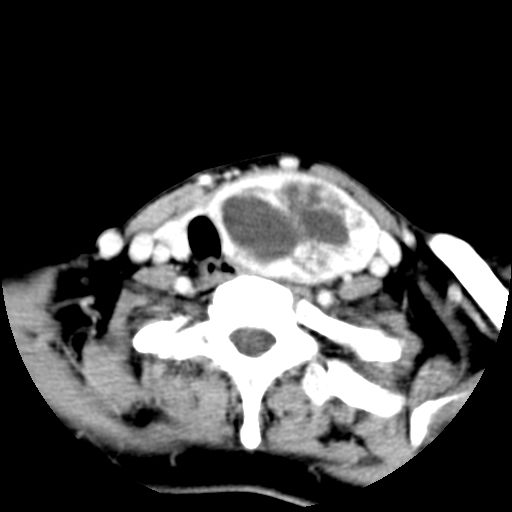

女  53岁  左侧甲状腺肿物3年,近2月明显增大。病理稍后发。

左侧甲状腺内见有一较大类圆形低密度区,边缘清楚光整,增强有一定强化,但仍较正常甲状腺组织强化弱,左侧甲状腺周围组织明显受压移位,且周围组织界限存在,周围组织间隙内未见肿大淋巴结,结合病史考虑为良性病变,左侧甲状腺腺瘤可能大。

左侧甲状腺内见有一较大类圆形低密度区,边缘清楚光整,增强有一定强化,但仍较正常甲状腺组织强化弱,左侧甲状腺周围组织明显受压移位,且周围组织界限存在,周围组织间隙内未见肿大淋巴结。

考虑:甲状腺囊腺瘤

双侧都有,最大病灶在左侧,其包膜和灶内部都有明显的强化,提示其血供丰富。我首先考虑是良性占位,以腺瘤可能性大。

左侧甲状腺内见有一类圆形低密度区,边缘清楚光整,可见明显增强,间隔亦可见增强,且与周围组织分解清晰,周围组织间隙内未见肿大淋巴结。右侧亦可见类似表现。考虑甲状腺腺瘤。

手术病理证实:双侧腺瘤样甲状腺肿。